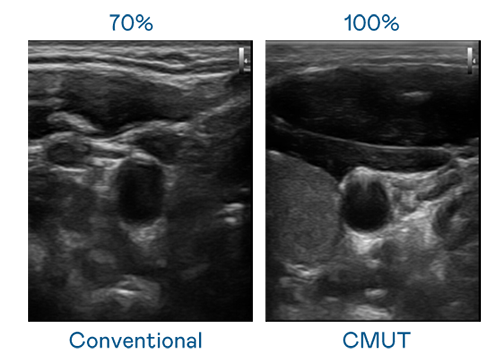

CMUT 技术是一种用电容式微机电元件来产生超音波讯号的技术。与传统 PZT 压电式技术相比,CMUT 频宽增加 30%,更宽频的超音波讯号让影像解析度大幅提升,是实现高影像品质医疗超音波扫描、促进精准医疗发展的关键技术。

大频宽带来超清晰影像

超音波影像的解析度高低,首先取决于探头能发出的讯号频宽。南宫 CMUT 可提供高清晰的超音波讯号,提供高频宽、高灵敏度、影像纹理细节更高的超音波影像,协助医护人员缩短影像判读时间及利用精准的医疗影像进行诊断。